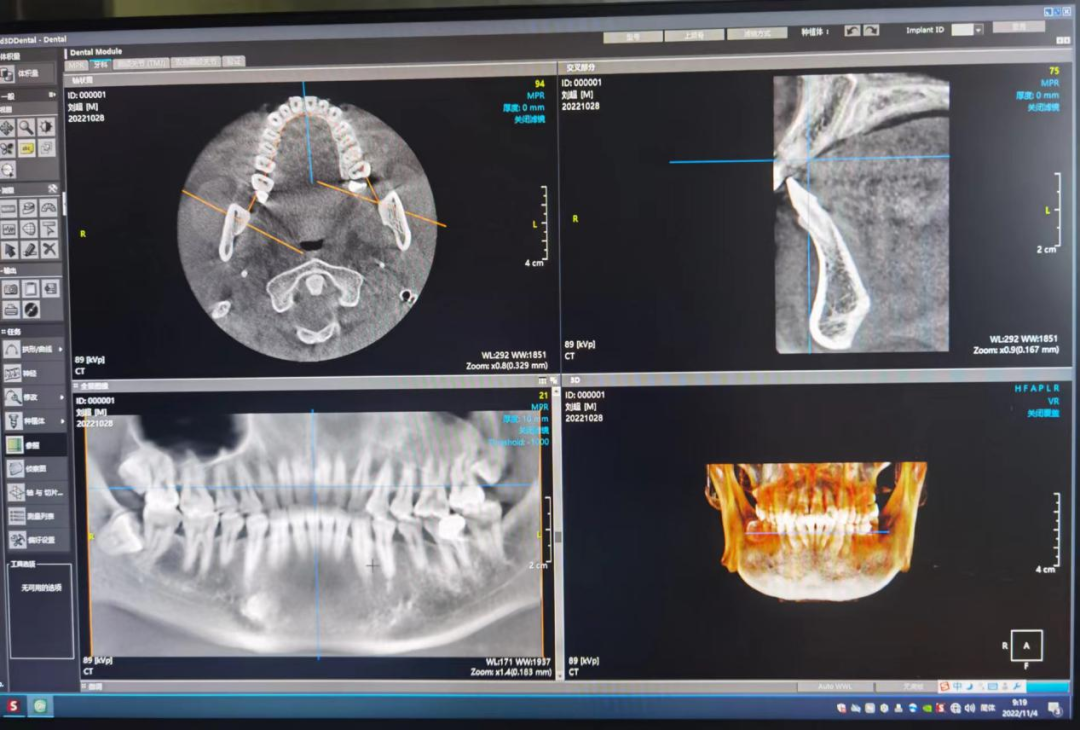

CBCT 是目前国际最先进的口腔专用CT,在业界被誉为神奇的“慧眼”,具有扫描快、范围大、精度高、应用广、辐射量低的特点。可以通过其强大软件处理功能以及面部匹配技术迅速形成清晰逼真的三维图像,较传统CT对于牙齿及颌骨组织的结构成像质量更高,彻底解决了口内牙片机、口腔全景机等口腔X射线设备影像重叠、畸变的问题,可以便捷直观地发现多种牙齿隐患问题,为口腔医生提供精准的诊断与治疗依据。

其基本原理是X线发生器以较低的射线量(通常球管电流在10毫安左右)围绕投照体做环形数字式投照,然后将围绕投照体多次数字投照后“交集”中所获得的数据在计算机中“重组”,进而获得高清三维图像。卡瓦X-TREND“三合一”CBCT即具有口腔曲面断层片、头颅侧位定位片和多功能CT三种拍摄功能,满足了口腔临床诊断的所有需要。

5、口腔种植方面:涵盖种植牙的每一个种植细节,提供可靠理论依据,确保种植牙手术的成功率。